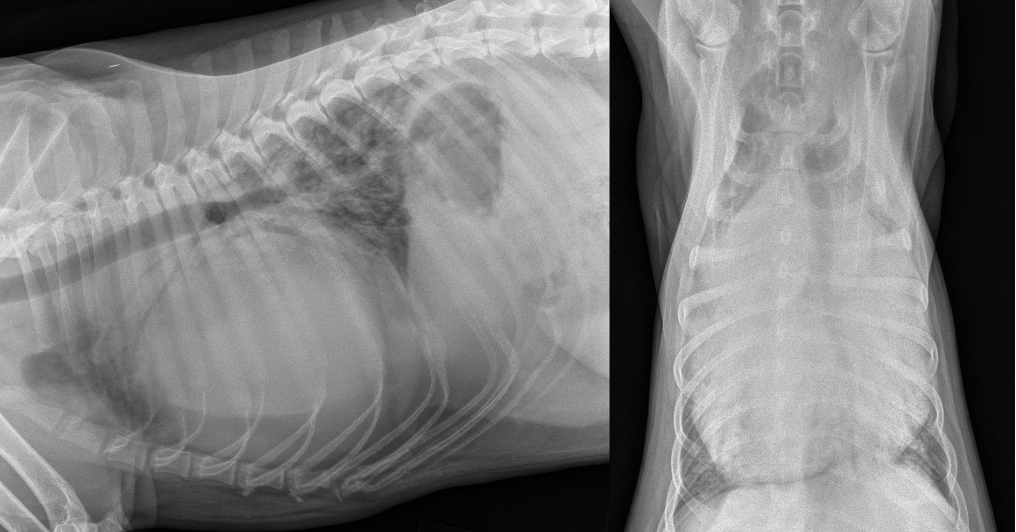

There are several congenital diseases of the pericardium recognized in small animals. Although peritoneopericardial diaphragmatic hernias (PPDH) are the most common type of congenital abnormality encountered (Figure 1), sporadic reports of partial pericardial defects and intrapericardial cysts have been published.2

Thoracic radiography usually demonstrates abnormalities when there is significant accumulation of pericardial fluid. The cardiac silhouette loses its angles and waists and becomes globe-shaped (Figure 3). Most cases are not "classic" and require integration with the other data. Pulmonary vascularity is often reduced from low cardiac output in contrast to congestive heart failure (CHF) from cardiomyopathy or valvular disease in which the pulmonary vascularity may be increased (especially the pulmonary veins).